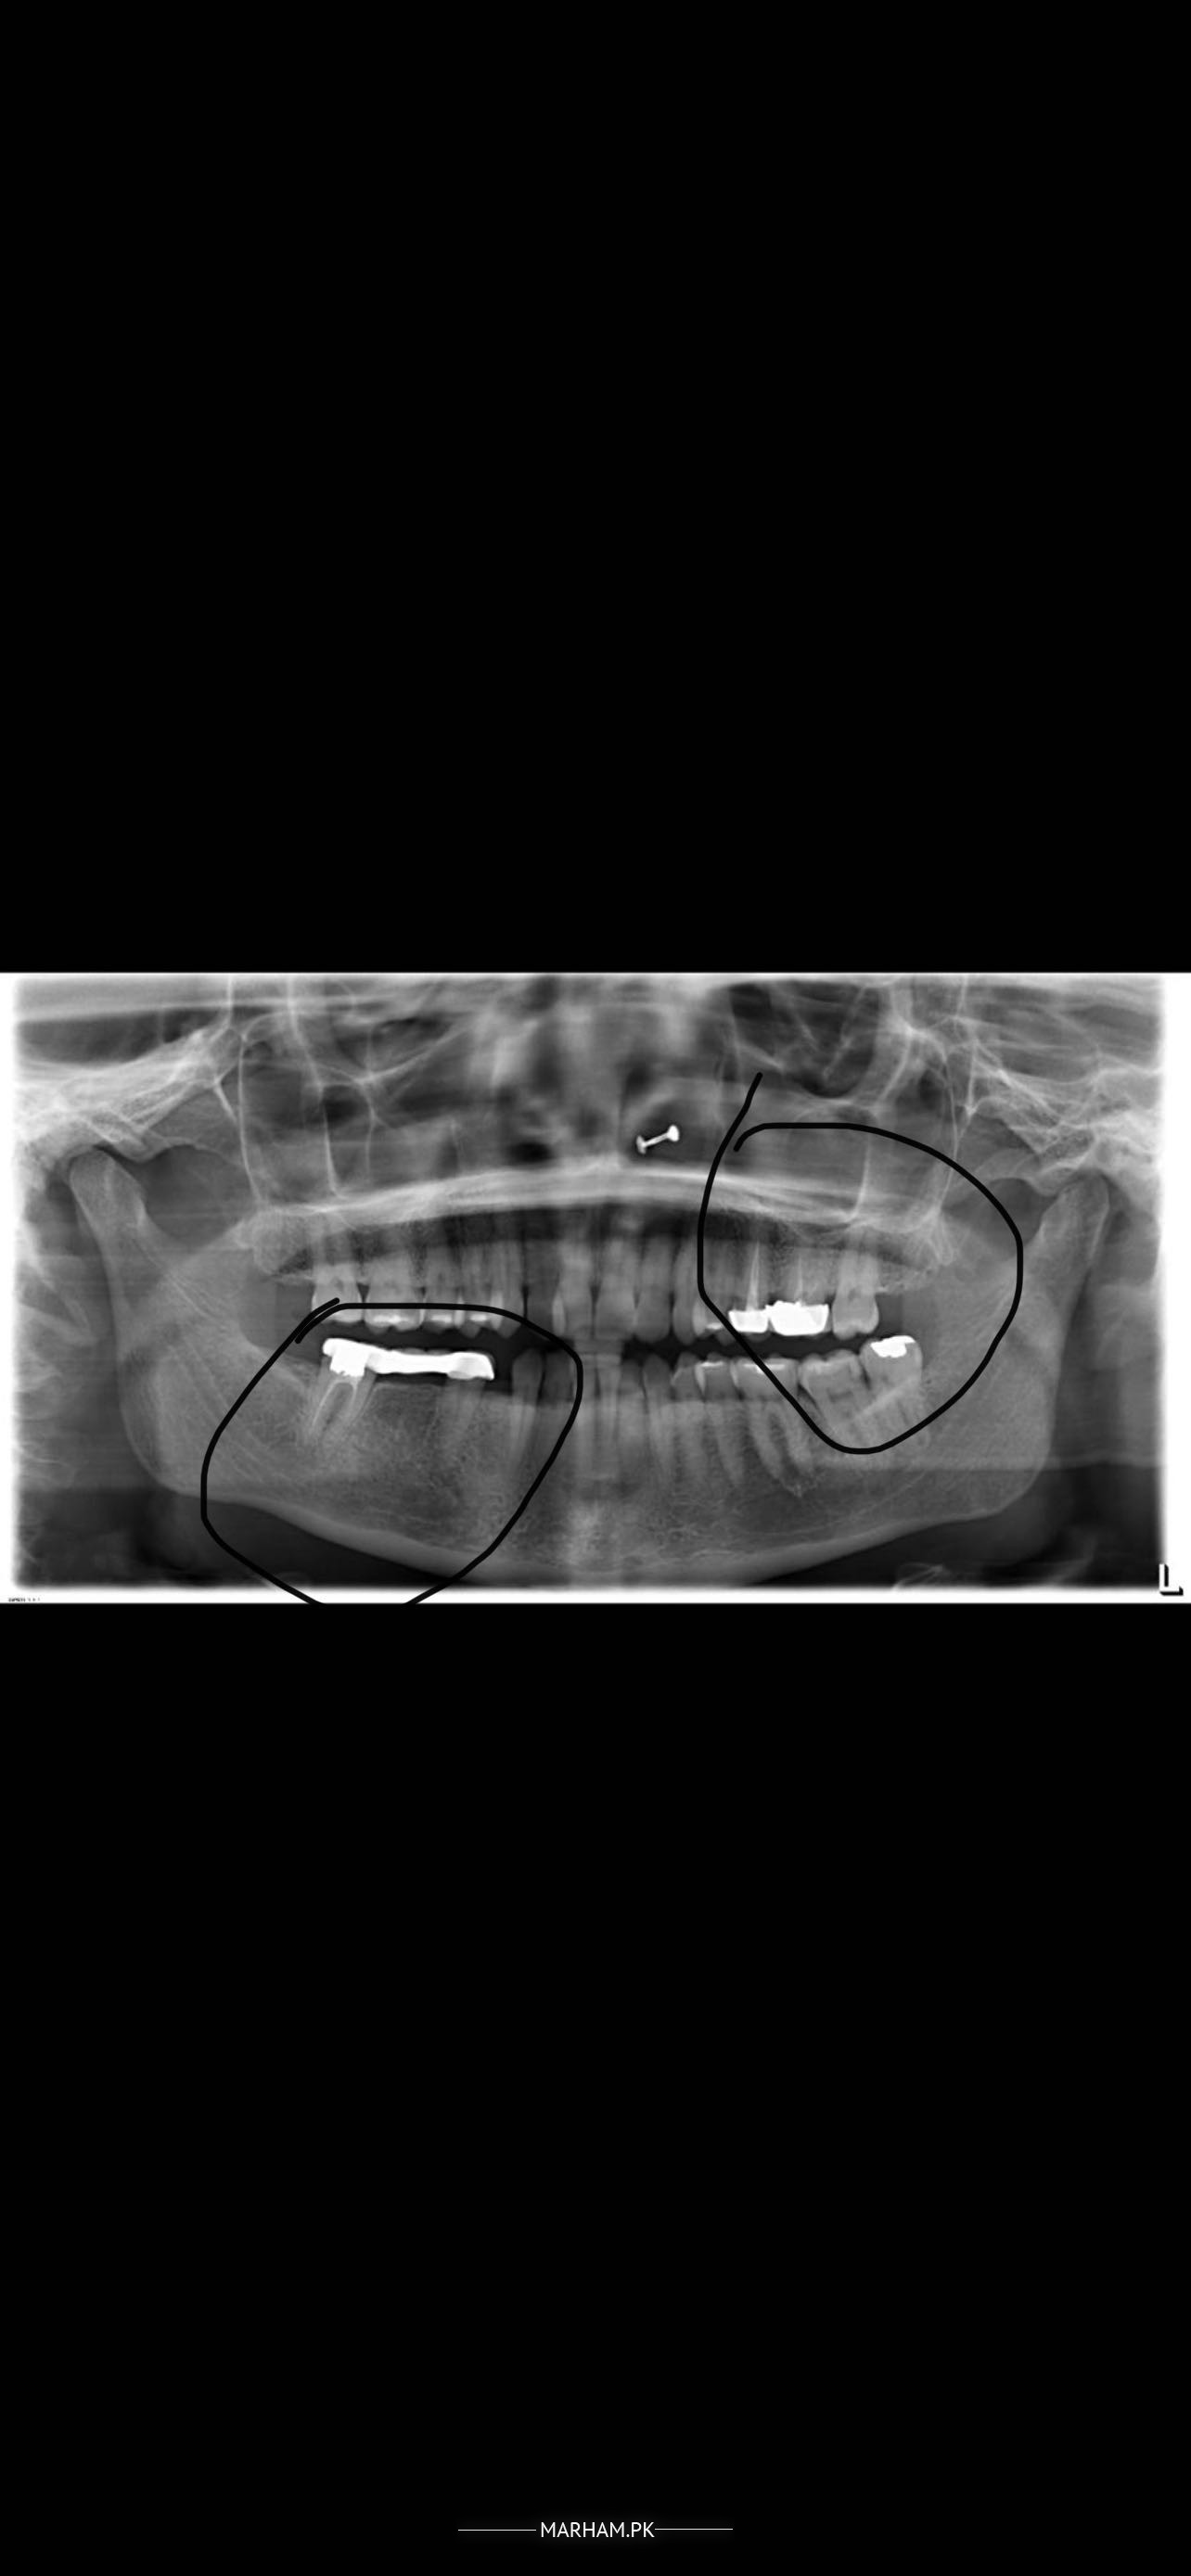

Hi Mn Australia mn rehti hon or mn ne Pakistan se almost 7 years back 2 root canal kerwai thin jis mn mujhe kabhi kabhi dard hota hai bohat halka sa or us pe cap bhi laga hoa hai … kisi or dant k dard ki waja se dentist k pas gai thi or unhon ne mujhe kaha k aapka Ye dant Sahi se nai kia dentist ne and u need to do it again but mujhe koi kaha dard nai hai….. same aisa hi mere dosri side pe masla hai jis mn bridge laga hoa hai… yahan dentist ne kaha k bridge bhi or jo left side pe two root canal hn dono k cover Sahi nai lage hoe… kindly suggest k mn kia karon … mn kitna arsa ise chor sakti hon bcz as such mujhe koi khas pain nai hAi… mn apni X-rays bhi send ker rahi hon kindly help me… I m so worried ?

agr pain nhi hai tu jab tak chalte hai chalaey....agr masla ana shuru ho gaya hai tu remove krwaye kyunke inki rct howi howi hai tu during removal ye tot skhte hai bki safai ka khayal rakhe...doc is right ye sahi nhi bne howe esp lower bridge upper wale crowns bi bulky hai with overhangs

ln my opinion as far as X-ray suggests us pain is due to pockets. Being on a conservative approach you must brush your teeth twice before going to bed and after breakfast. Use a tooth paste containing chlorhexidine for at least 2 weeks. And also use an antibacterial mouthwash twice a day. Use this protocol for 2 weeks then plan a procedure if your symptoms persists.

W/salam , ap k right aur left dono bridges ki root canal poor hui v hai. Thats not complete yet jis ki waja se ye failure mai ja skti hai aur right lower side p periapical changes already agai han due to infection. Agar ap bridge ni utarwana chahtin to drill k sth bridge k oper se b root canal ki ha skti hai. Aur ye yad rakhain k jab bhi ap root canal treatment krwain to X-Ray mai lazmi confirm krein k roots properly end tk fill hui han ya ni . Thanks

the Root canal on the left upper molar as lower right molars are not done properly and the bridge work is also not done properly. if you don't have Persistent pain and discomfort in both sides while eating or at rest. then it can be delayed till you feel discomfort/pain, as the treatment had been done 7 yrs ago,but do improve your oral hygiene routine by brushing twice daily,floosing daily at bed time and.

Once u develop problem then u will have to get them Re-Root canalled and new crowns and bridgework.

The root canals are not that good. True but they need further examination and testing. There is a premolar thats included in your bridge and its not endo treated. A clinical exam would further clear the picture and diagnosis.